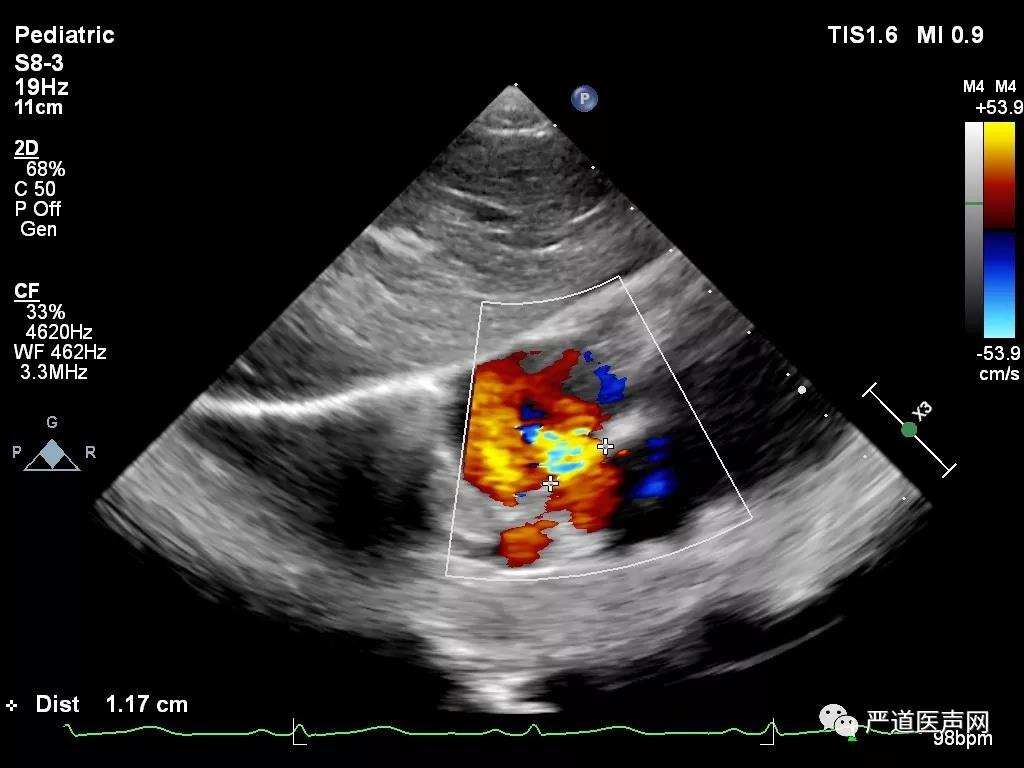

术前超声测量

术中超声显示:房间隔缺损,继发孔型,大小12mm,右心导管检查提示Qp/Qs:1.45,肺动脉压力28/9 (18)mmHg,建立钢丝轨道,选择6F MPA2导管,经房间隔缺损送入左房,置于左上肺静脉,并导入输送钢丝0.035/260cm。

超声心动图提示伞盘位置良好无残余分流后,进一步逆时针旋转控制手柄,解脱输送钢缆和封堵器栓头的连接,释放封堵器。

术后经胸超声心动图提示封堵器位置稳定,房间隔分流消失,封堵器不干扰心脏瓣膜等心内结果,手术效果满意。